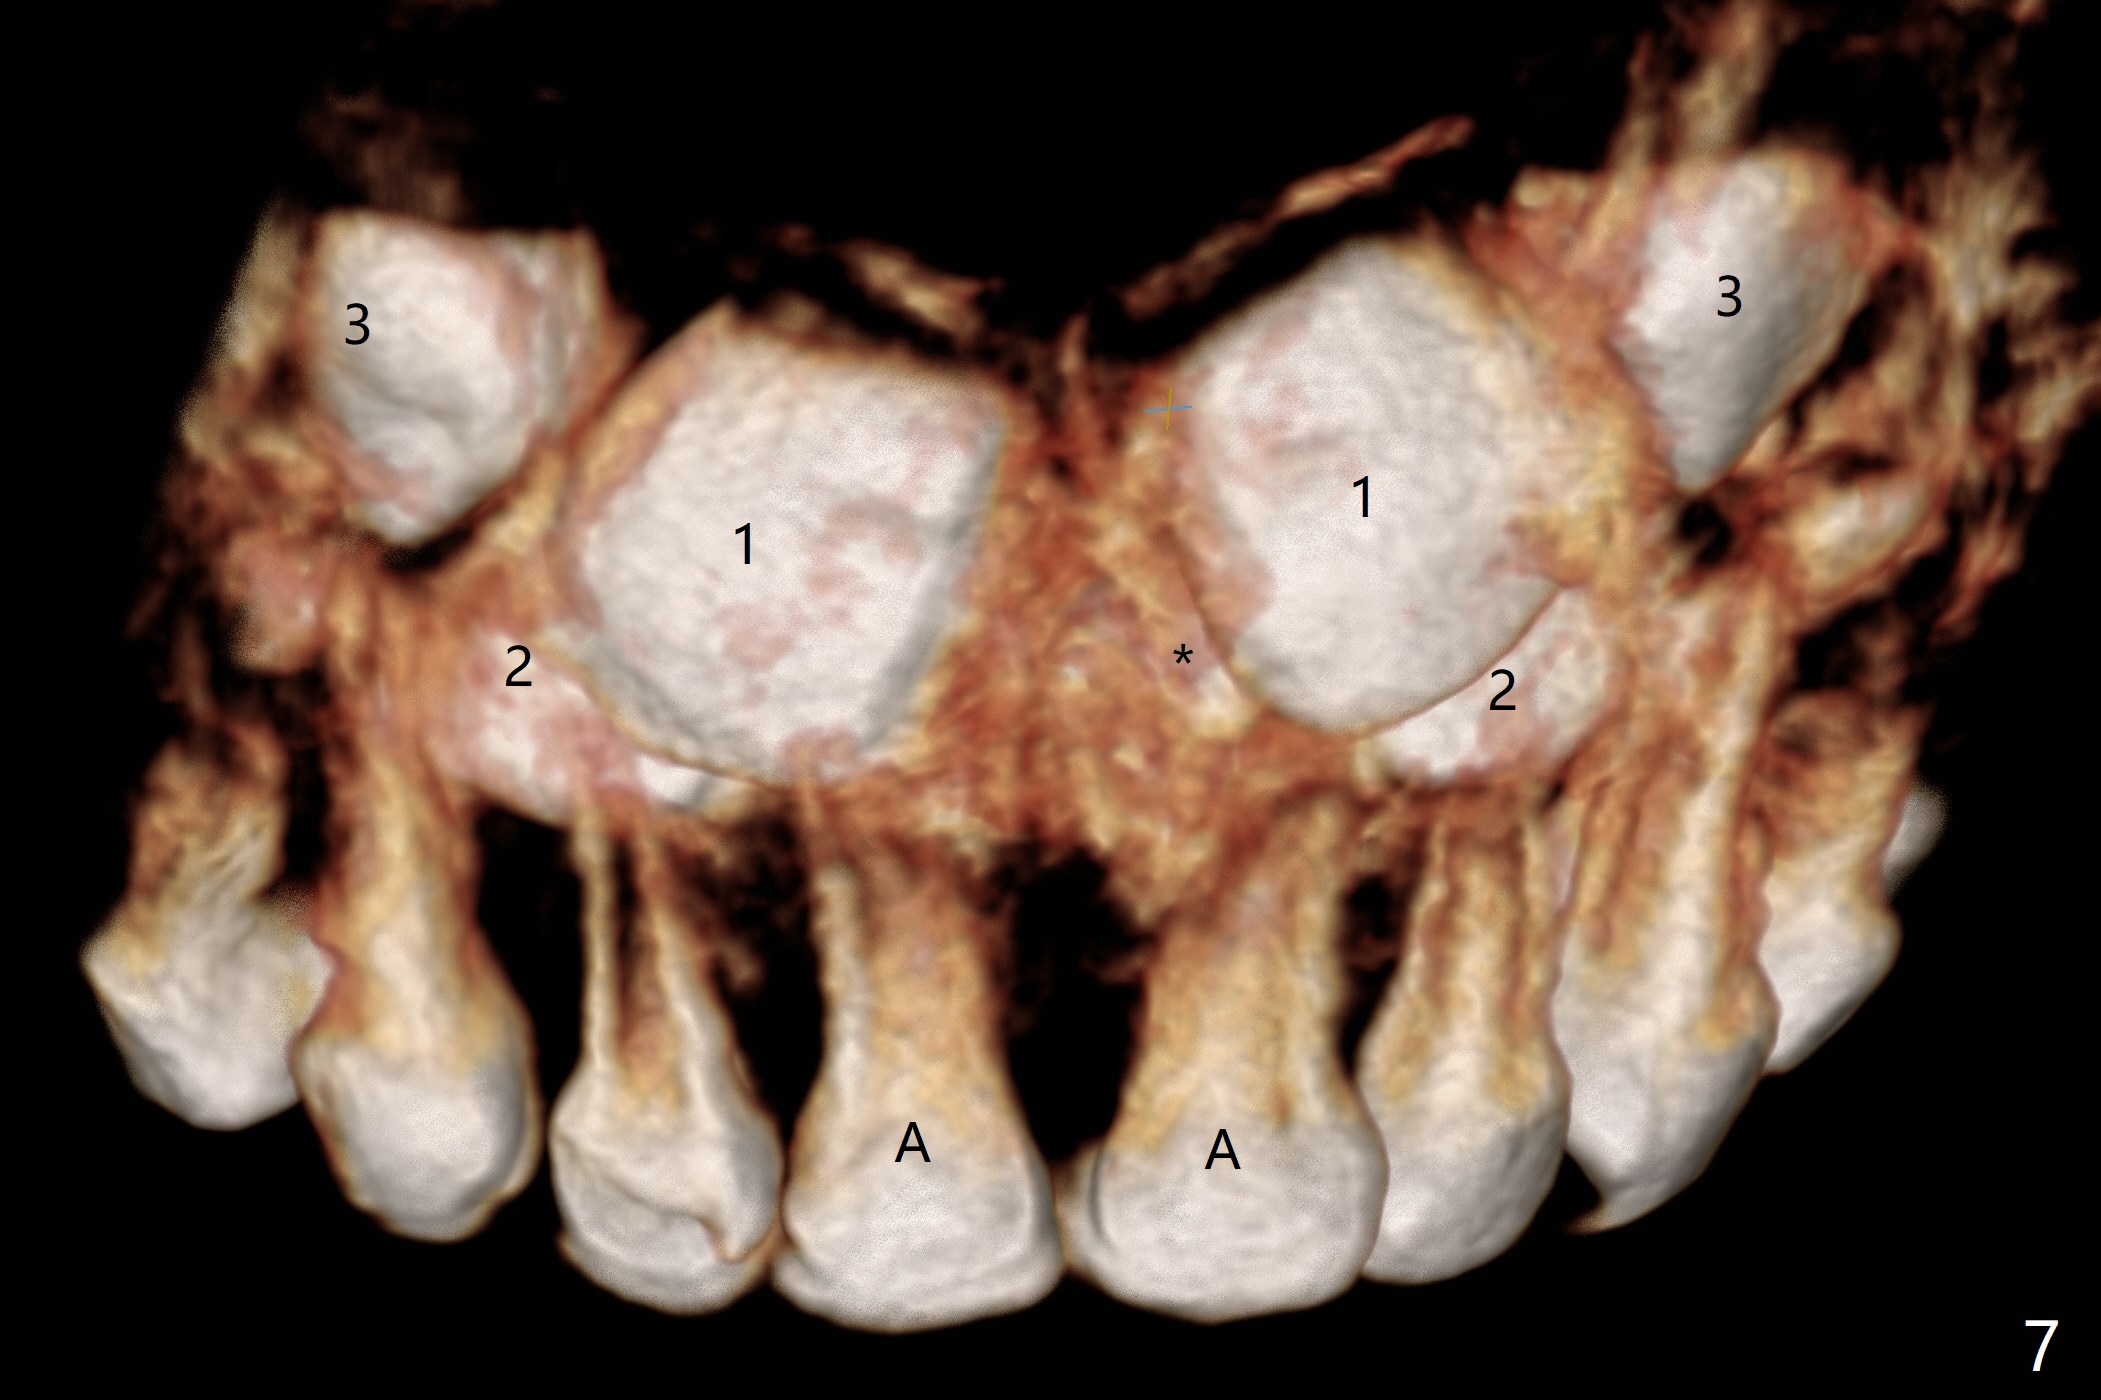

Reanalysis of 3 D images (Fig.7 (frontal view), 8 (posterior view), 9 (lateral view), 10 (lateral view with section) of CT taken 1 year 3 months earlier shows that the mesiodens (*) and the permanent lateral incisors (2) are palatal to the permanent central incisors (1) and canines (3) and the deciduous central incisors (A).  The supernumerary teeth do block the eruption of the permanent central incisors (Fig.10).